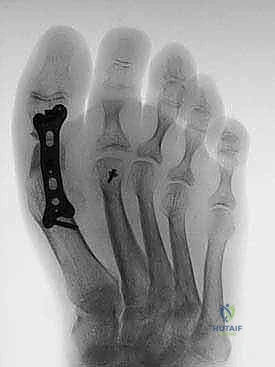

6. التثبيت الداخلي الصلب (Rigid Internal Fixation)

لضمان التئام العظام (وهو ما يستغرق عدة أسابيع)، يجب تثبيت المفصل والطعم العظمي بقوة شديدة. يستخدم الأستاذ الدكتور محمد هطيف أحدث الشرائح المعدنية المصممة خصيصاً لاندماج إبهام القدم (Anatomical Locking Plates) والمسامير التيتانيوم. يتم وضع الشريحة فوق المفصل وتثبيتها بمسامير تمر عبر الطعم العظمي لضمان ثباته المطلق.

7. الإغلاق والتحقق بالأشعة

يتم أخذ صور أشعة سينية داخل غرفة العمليات (Fluoroscopy) للتأكد من المحاذاة المثالية للإصبع، وتصحيح زاوية الارتفاع، والموضع الدقيق للمسامير. بعد ذلك، يتم إغلاق الجرح بخيوط تجميلية ووضع ضمادات معقمة وجبيرة واقية.